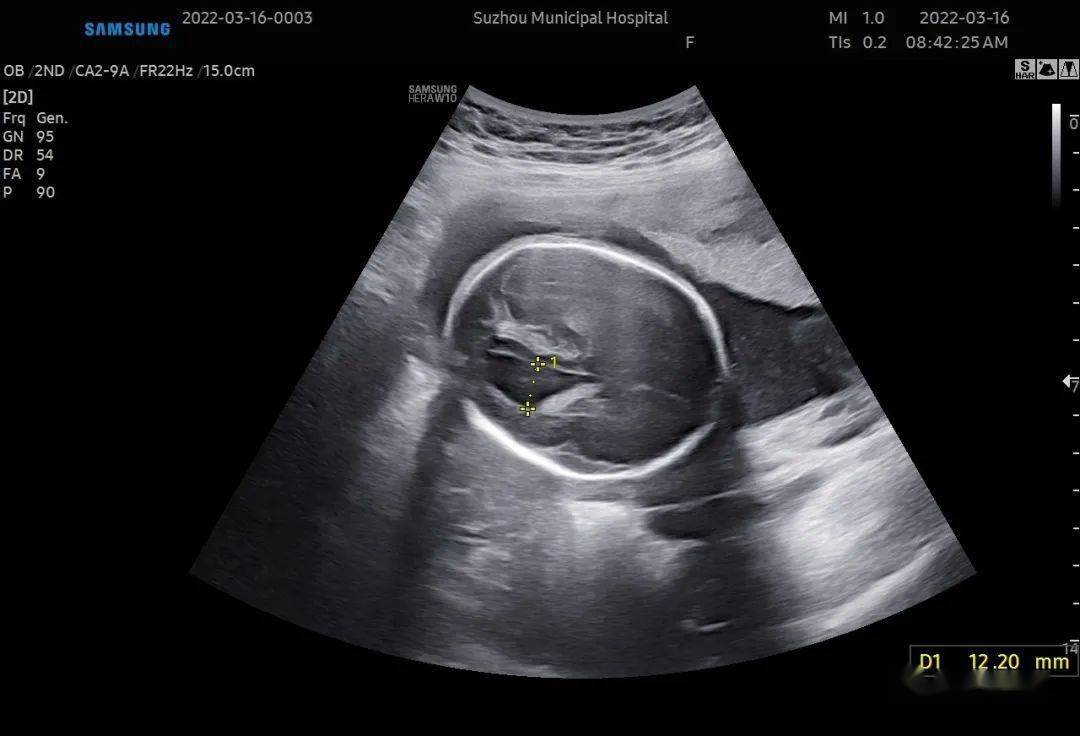

胎儿柠檬头图片

柠檬头,常常合并香蕉小脑,脑积水和开放性脊柱裂.

胎儿颅骨形状异常之柠檬头和草莓头